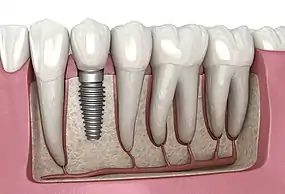

A dental implant (also known as an endosseous implant or fixture) is a prosthesis that interfaces with the bone of the jaw or skull to support a dental prosthesis such as a crown, bridge, denture, or facial prosthesis or to act as an orthodontic anchor. The basis for modern dental implants is a biological process called osseointegration, in which materials such as titanium or zirconia form an intimate bond to the bone.[1] The implant fixture is first placed so that it is likely to osseointegrate, then a dental prosthetic is added. A variable amount of healing time is required for osseointegration before either the dental prosthetic (a tooth, bridge, or denture) is attached to the implant or an abutment is placed which will hold a dental prosthetic/crown.

Single tooth restorations are individual freestanding units not connected to other teeth or implants, used to replace missing individual teeth.[12] For individual tooth replacement, an implant abutment is first secured to the implant with an abutment screw. A crown (the dental prosthesis) is then connected to the abutment with dental cement, a small screw, or fused with the abutment as one piece during fabrication.[16]:211–232 Dental implants, in the same way, can also be used to retain a multiple tooth dental prosthesis either in the form of a fixed bridge or removable dentures.